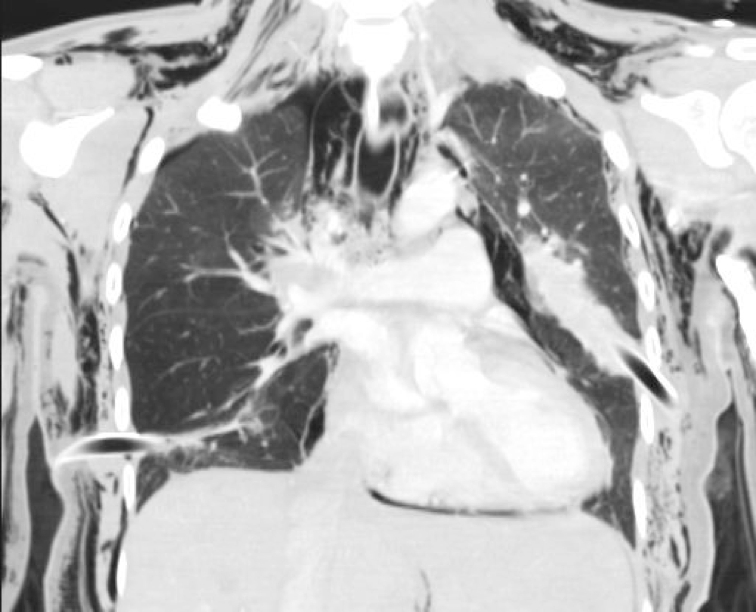

Computed tomography of the cervical spine, chest (Box 2) and abdomen showed injuries involving the spine, ribs, sternum, lungs and liver (Box 3).

2 Coronal computed tomography of the chest showing residual right-side pneumothorax, pneumomediastinum, extensive bilateral subcutaneous emphysema and bilateral intercostal catheters

- Left haemopneumothorax

- Right pneumothorax and pneumomediastinum

- Bilateral pulmonary contusions

- Extensive bilateral lower lobe collapse

- Periportal oedema of the liver

- Extensive subcutaneous emphysema